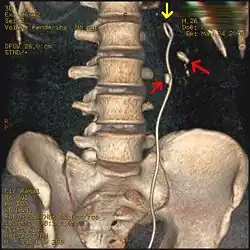

Three-dimensional reconstructed CT scan image of a ureteral stent in the left kidney (indicated by yellow arrow), with a kidney stone in the inferior renal pelvis (highest red arrow) and one in the ureter beside the stent (lower red arrow)

Ureteroscopic surgery

Ureteroscopy has become increasingly popular as flexible and rigid fiberoptic ureteroscopes have become smaller. One ureteroscopic technique involves the placement of a ureteral stent (a small tube extending from the bladder, up the ureter and into the kidney) to provide immediate relief of an obstructed kidney. Stent placement can be useful for saving a kidney at risk for postrenal acute kidney failure due to the increased hydrostatic pressure, swelling and infection (pyelonephritis and pyonephrosis) caused by an obstructing stone. Ureteral stents vary in length from 24 to 30 cm (9.4 to 11.8 in) and most have a shape commonly referred to as a "double-J" or "double pigtail", because of the curl at both ends. They are designed to allow urine to flow past an obstruction in the ureter. They may be retained in the ureter for days to weeks as infections resolve and as stones are dissolved or fragmented by ESWL or by some other treatment. The stents dilate the ureters, which can facilitate instrumentation, and they also provide a clear landmark to aid in the visualization of the ureters and any associated stones on radiographic examinations. The presence of indwelling ureteral stents may cause minimal to moderate discomfort, frequency or urgency incontinence, and infection, which in general resolves on removal. Most ureteral stents can be removed cystoscopically during an office visit under topical anesthesia after resolution of urolithiasis.[116] Research is currently uncertain if placing a temporary stent during ureteroscopy leads to different outcomes than not placing a stent in terms of number of hospital visits for post operative problems, short or long term pain, need for narcotic pain medication, risk of UTI, need for a repeat procedure or narrowing of the ureter from scarring.[117]